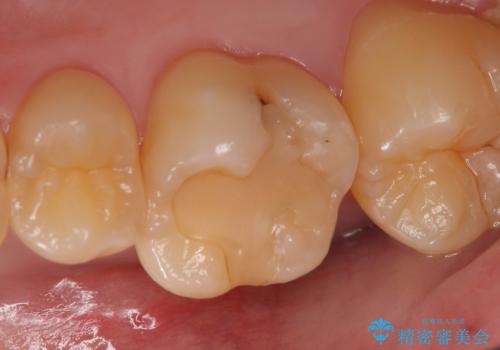

前歯のレジン前装冠(保険内)によるブリッジは、金属で裏打ちされており透明感がなく不自然で、ポンティックも必要以上に長く作られていました。

古いブリッジと金属の土台を除去し、ファイバーコア(金属を使わない強くてしなやかな土台)を植立したのち、オールセラミックのブリッジによる補綴治療を行いました。。